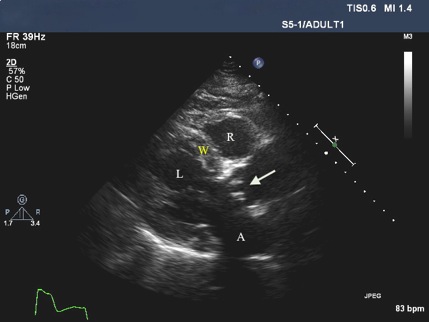

On physical examination, the patient had a blood pressure of 140/82 mm Hg, a heart rate of 78 beats per minute, and a respiration rate of 18 breaths per minute. Inspection of her neck showed jugular venous distention. Chest auscultation revealed bilateral rhonchi at the lung bases. On cardiac examination, there was a regular rhythm with a grade III/VI systolic murmur heard loudest at the left sternal border with transmission across the precordium and to the neck. On extremity examination, mild pedal edema was present bilaterally. An electrocardiogram showed a paced rhythm and a chest radiograph revealed congestive changes in the lung fields bilaterally. Laboratory examination demonstrated a normal complete blood count, electrolytes, and renal function, but an elevated brain-type natriuretic peptide of 1128 pg/mL (normal, <107 pg/mL), which is consistent with congestive heart failure. A two-dimensional transthoracic echocardiogram with color Doppler flow mapping demonstrated left ventricular hypertrophy with normal left ventricular systolic function and severe stenosis of the bioprosthetic aortic valve (Figures 1 and 2). There was a peak systolic gradient across the valve of 81 mm Hg, a mean aortic valve gradient of 43 mm Hg, and a calculated aortic valve area of less than 0.5 cm2.

Figure 1. Echocardiogram showing a peak systolic gradient across the bioprosthetic aortic valve (arrow) of 81 mm Hg, a mean aortic gradient of 46 mm Hg, and an aortic valve area of less than 0.5 cm2.

Figure 2. Echocardiogram showing the right ventricle (R) and left ventricle (L). The thickened left ventricular wall is consistent with left ventricular hypertrophy (W). The left atrium (A) demonstrates normal size limits. There is evidence of calcification of the bioprosthetic aortic valve (arrow).